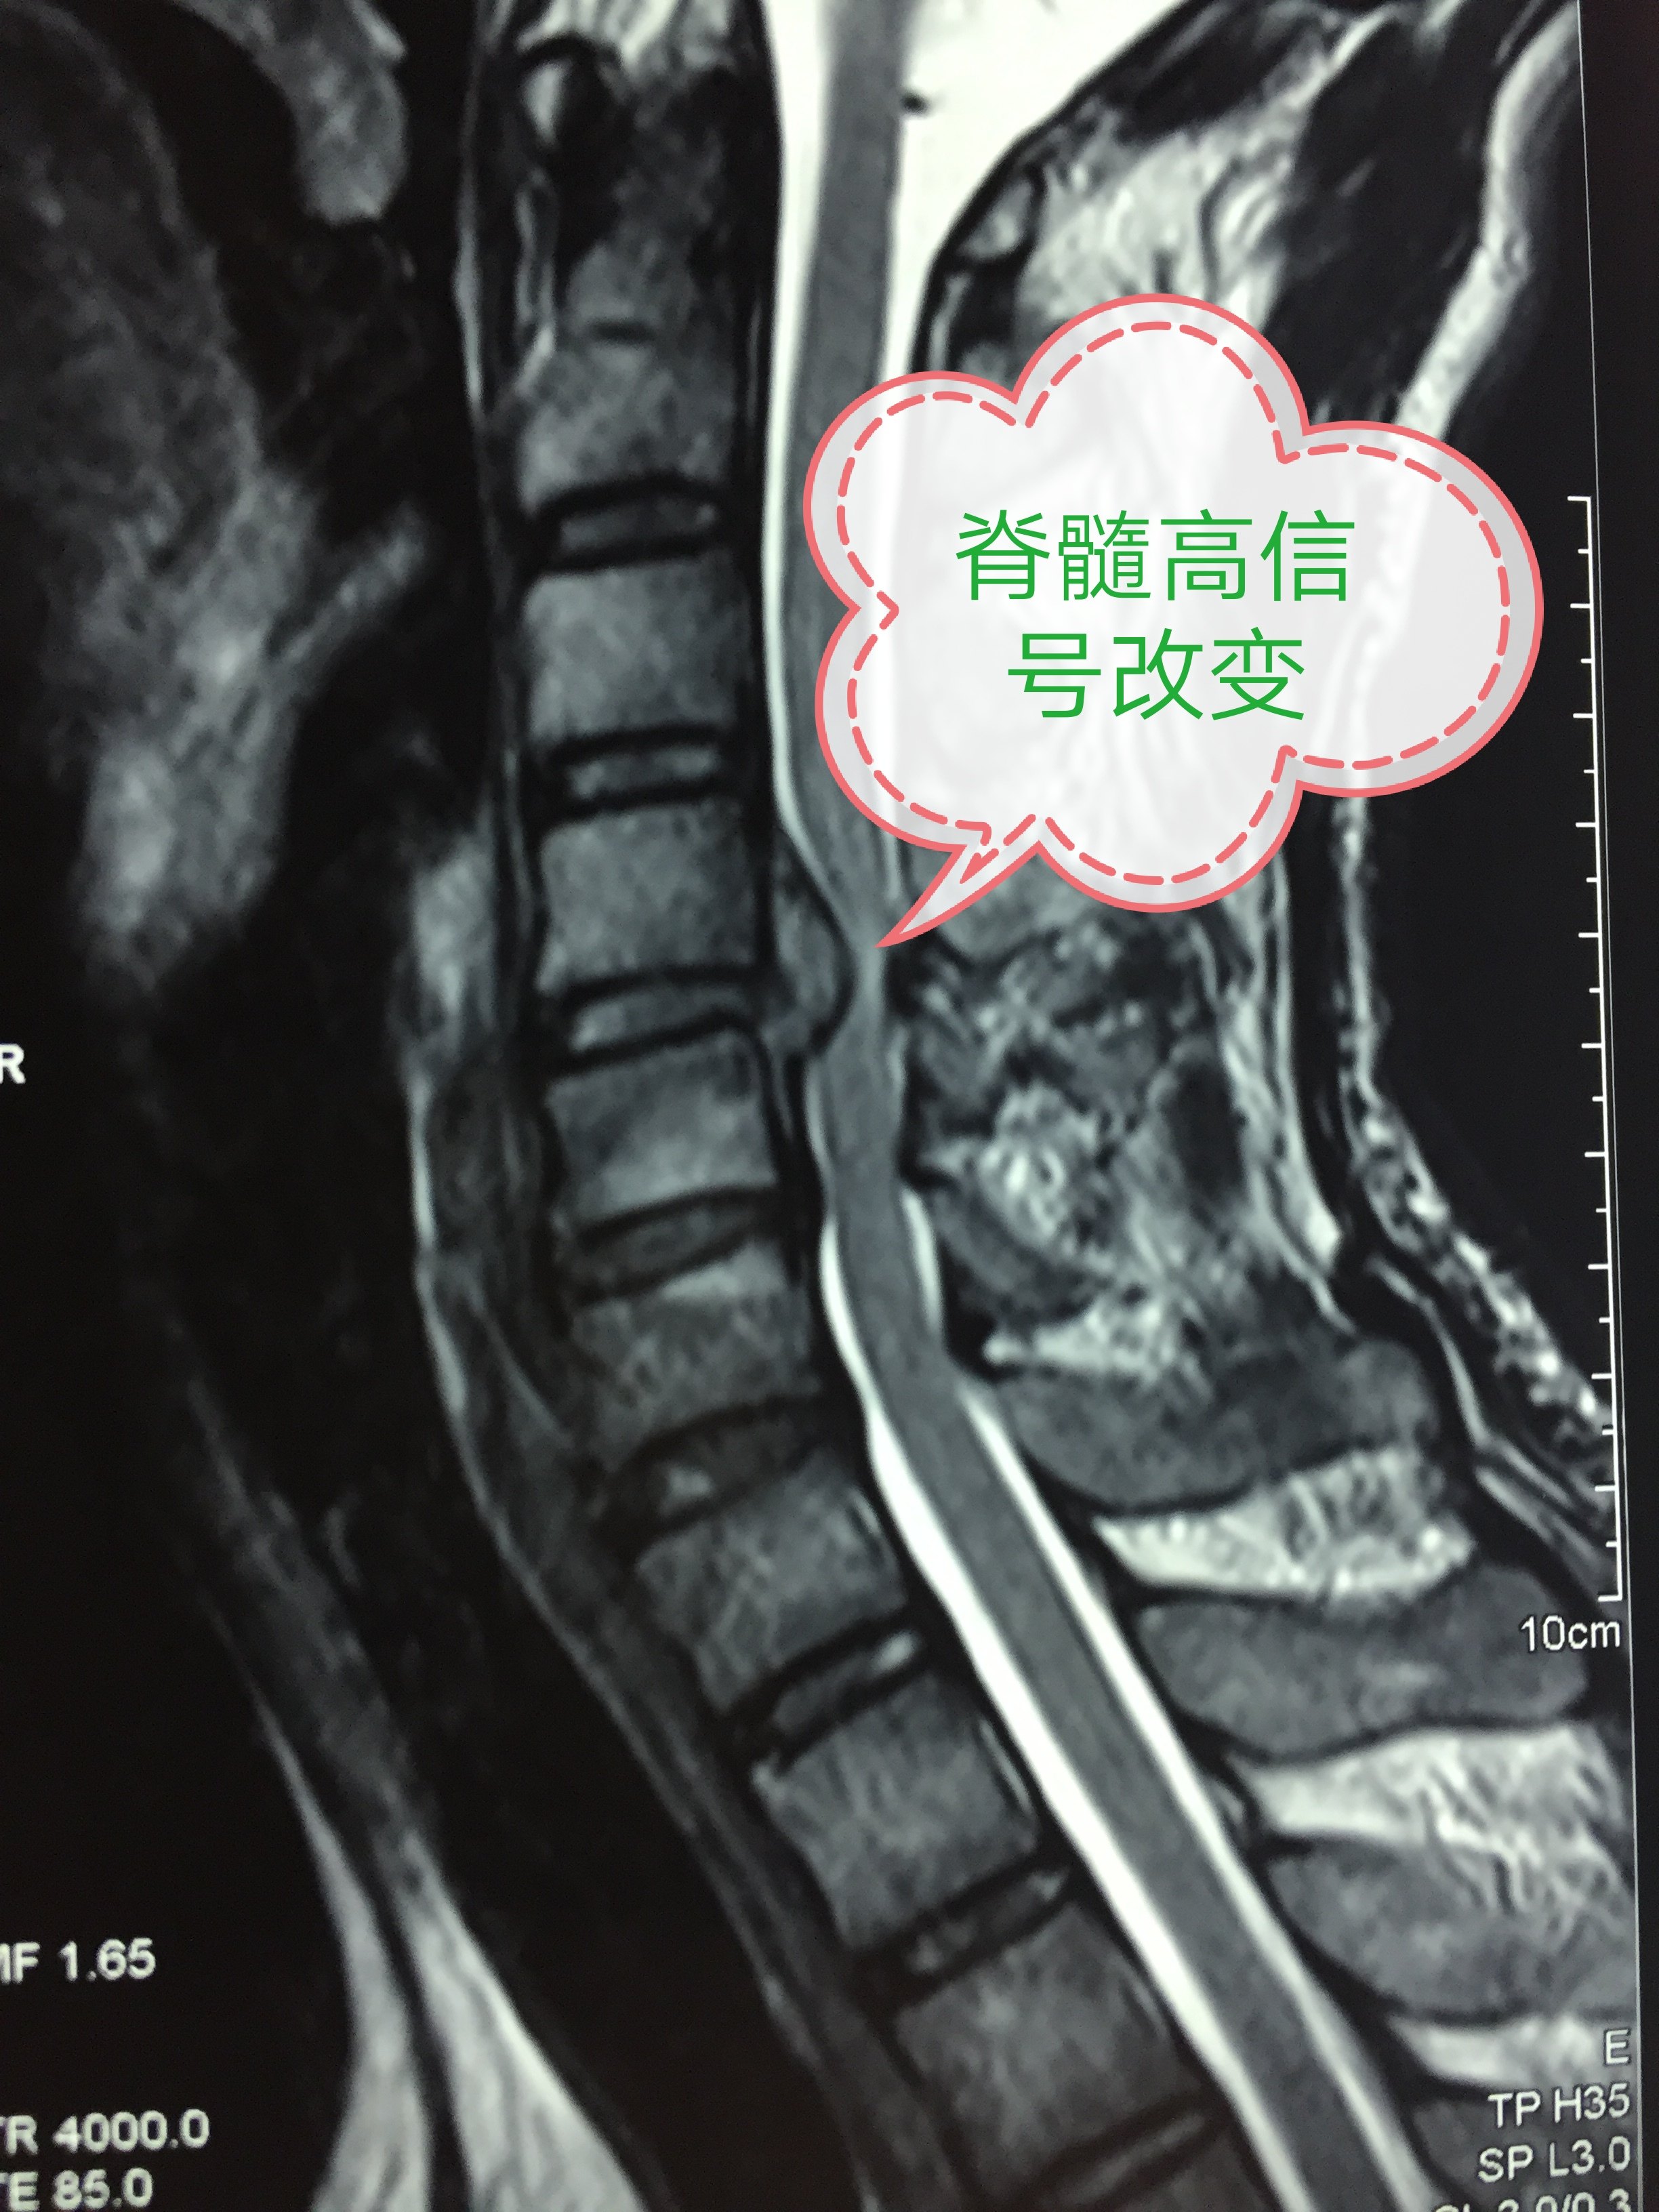

出现以上症状,应尽快找骨科(脊柱外科)医生就诊。拍颈椎X线片和MRI检查,不建议做CT检查(CT不能很好显示脊髓和神经,CT只是明确是否有骨赘)。颈椎X线片出现椎体有骨刺,颈椎变直甚至出现反弓。颈椎MRI显示椎间盘变性突出(图1),椎管内白色的脑脊液被阻断,脊髓和/或神经被压迫移位变性(图2),严重出现脊髓局部变白,这提示神经变性坏死(图3)。